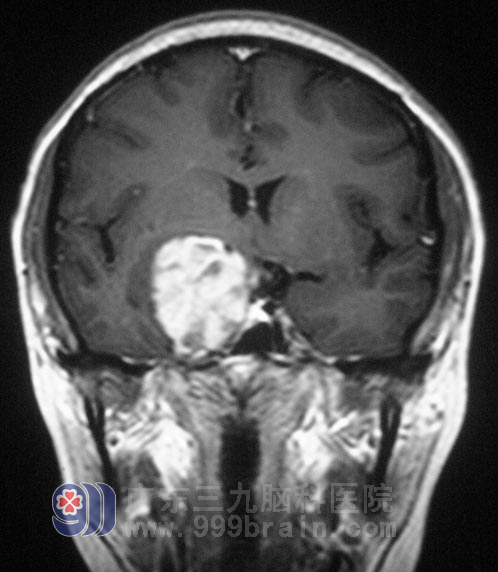

李女士, 32岁。大约半年前,开始出现月经不调,经量明显增多,且伴有口渴多饮,无多尿,当地医院妇科检查,无明显异常,未做特殊治疗;头颅MRI检查发现右侧蝶骨嵴占位性病变,约4cm×4cm×3cm,向鞍区侵犯,考虑脑膜瘤可能性大,被认为手术风险太大。

7月,李女士来到广东三九脑科医院综合神经外科就诊,鲁明主任阅片后初步判断为神经鞘瘤可能性大。完善相关检查后,7月8日,由鲁明主任主刀,在全麻下行右侧海绵窦内占位性病变切除术+颅底重建术+颅内压检测仪植入术,术中见肿瘤位于海绵窦内,色白,质韧,边界清楚,肿瘤包绕动眼神经。在显微镜下切除肿瘤,整个手术过程顺利。病理结果为:(海绵窦内)神经鞘膜瘤。术后李女士顺利渡过出血、感染、水肿期,已办理出院手续。

▲手术前